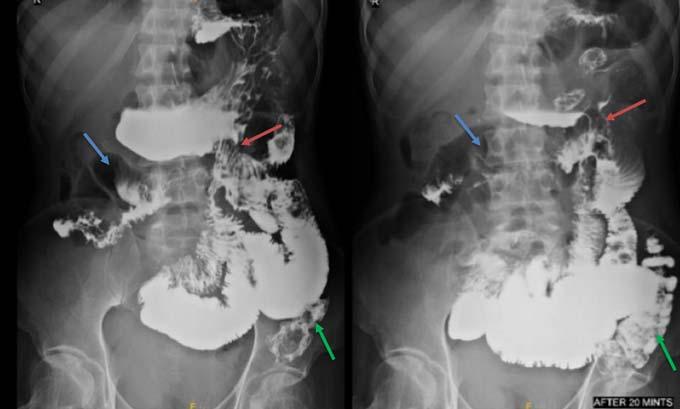

Among the metabolically abnormal patient’s population 20% (n=3) had Hypoglycemia, 40%(n=6) presented with Dyselectrolytemia, 26.67% (n=4) had Uremia, 13.33% (n=2) presented with Hepatic encephalopathy. Overall, 31 patients underwent Lumber puncture, of which CSF report shows abnormality in 11 (35.48%) cases and normal in 20 patients (64.51%). Abnormal CSF report suggesting viral meningoencephalitis found in 46% (n=5), bacterial meningitis in18% (n=2), Tuberculous Meningitis in 27% (n=3), Aseptic meningitis in 9% (n= 1). All 65 subjects underwent CT scan brain among which MRI Brain also done in 55 cases. CT findings is normal in 44.62% (n=29), abnormal in 55.38% (n=36). The most common CNS lesion on CT scan was infarction in 10.77% followed by ring lesion in 9.23% and intracerebral Hemorrhage in 7.96%. We observed cerebral infarction is causative factor of Seizure in female (15%) but intracerebral hemorrhage and ring lesion are most common findings in male, comprising 11.11% patients at each category. The CT scan in new onset Seizure of elderly patient population revealed Infarction in 28.57%, Gliosis in 19.04% and cerebral atrophy in 14.28%. The breakup of findings in MRI Scan of 55 patients shows Hyperintensities on T2, indicating Demyelination / Inflammation/edema in12.31% followed by infarction in 10.77% and ring lesion in 9.23%. In the female population, hyperintensities on T2 MRI found in 15% and Infarction in 15% whereas among the males intracerebral Hemorrhage, Ring lesion and hyperintensities on T2 found at similar occurrence rate @11% in each of these three types of lesions. EEG was done on 80% patients (n=52) of whom 22 patients has abnormal discharge in EEG but 30 patients have normal presentation. Among 65 patients one female expired due to Acute Demyelinated Encephalomyelitis (ADEM) and two males expired one due to Hemorrhage, another one with CNS infection when undergoing treatment indoor.

We found a strong positive correlation between abnormal EEG and abnormal Neuroimaging with Correlation coefficient of 0.902, (P- Value 0.0138) but almost no correlation found between normal EEG with normal Neuroimaging (Figs 1-4).